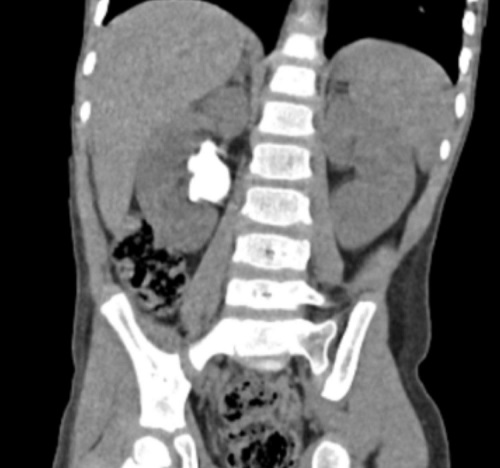

El paciente es derivado a Cirugía pediátrica, donde se le pide una tomografía computarizada (TC) de abdomen para corroborar el hallazgo. En este se observa litiasis pseudocoraliforme en la pelvis renal derecha de 37 mm de diámetro longitudinal con ectasia pielocalicial y múltiples litiasis en grupos caliciales medio e inferior derechos (Figura 1).

| Figura 1. Litiasis urinaria por cistinuria. Imagen de TC del paciente, donde se observa litiasis renal derecha coraliforme |